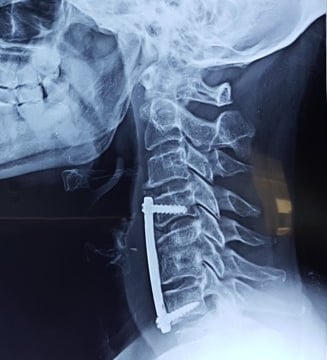

Our Team take a comprehensive and patient-focused approach to spinal health, offering a full spectrum of treatments—from non-surgical therapies to advanced surgical procedures. Our goal is to provide personalized care that prioritizes your comfort, recovery, and long-term well-being. We specialize in a variety of spinal procedures, including Anterior Lumbar Interbody Fusion (ALIF), Posterior Lumbar Interbody Fusion (PLIF), and other state-of-the-art surgical techniques. Understanding your treatment options is essential, and we are committed to equipping you with the knowledge and guidance needed to make informed decisions about your spinal health. With a focus on expertise, innovation, and compassionate care, we are here to support you on your journey toward a pain-free and active life.

Minimally Invasive Spinal Surgery

Revision Spinal Surgery

Complex Spinal Deformity Surgery